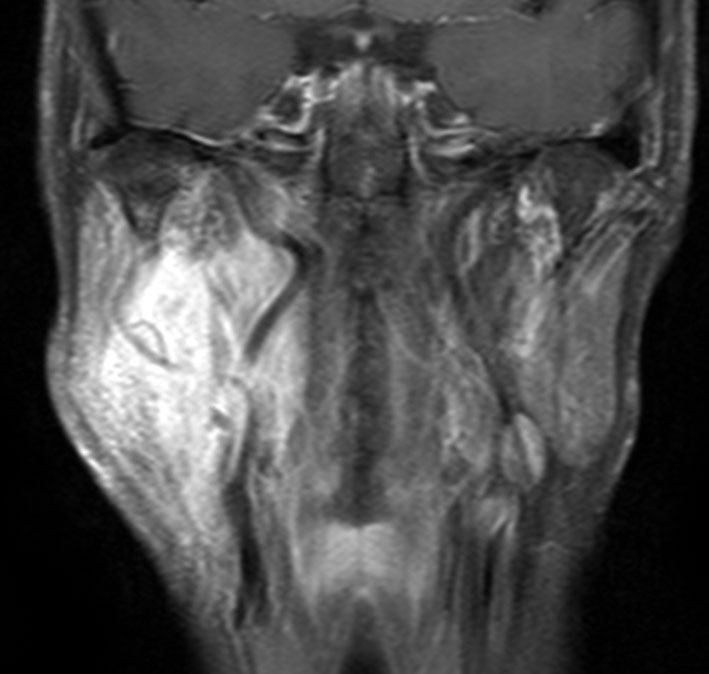

右はがドリニウム増強MRIです。NF-1患者さんの右深頸部のplexiform neurofibromaに発生したものです。通常の神経鞘腫に比較して境界が不鮮明で増大速度が早いことが特徴です。

- MRIでは境界不鮮明な不規則に増強される腫瘍です

- 細い神経の分枝に沿って周囲に非常に広範囲に広がっています

- 周囲軟部組織,神経組織を巻き込んで浸潤していますので,剥離操作で摘出することができません